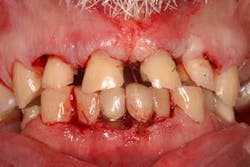

Case study A 58-year-old male with a noncontributory medical history presented to a private practice for a complete rehabilitation of his dentition due to years of bruxism and parafunction. (Fig. 1) After surgical and restorative consultations, a treatment plan was fabricated. The treatment plan included restoring his lost vertical dimension, restoring his natural dentition with porcelain-fused-to-metal full-coverage crowns, and replacing his lost posterior teeth with dental implants. After his vertical dimension was restored with an acrylic bite plate to a position harmonious with TMJ function, crown-lengthening surgery was performed. (Fig. 2)Fig. 2 Six weeks after, the teeth were temporized to develop soft tissue margins/interdental papillae. (Figs. 3 and 3a) The patient was kept in temporaries for three months, during which time an implant was placed in site No. 19. Both the natural dentition and the implant were completed at the same time, three months after implant placement. (Fig. 4) Because of the patient’s occlusal issues, the implant was screw-retained, and the patient was given a maxillary night guard. Three weeks after insertion, the patient presented with a loose abutment screw. The dentist tightened the screw and sent the patient home. This cycle was repeated two more times until the patient presented again with a loose crown, but this time, a fracture implant screw. The dentist attempted to remove the screw with a Cavitron and drilling the implant screw out to release preload, but to no avail. The case was then referred to my office for implant removal.